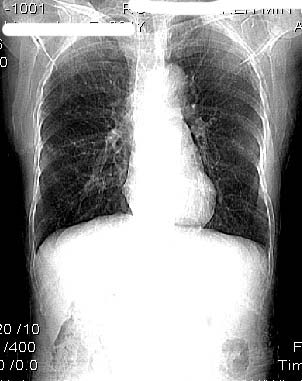

女:61岁.腹痛腹胀20天,行b超腹膜后实性占位.扫完后我查体发现患者右颈根部约3厘米类圆性包块,有移动{我考虑右颈根部包块是肿大淋巴结}.

ct:肝胃之间、胰头后、腹主a周围,融合而成团块状影,包绕血管,胰腺前移后缘分界欠清,与肝胃分界清,肿块未见明显强化,肝右叶后段小囊肿。

女:61岁.腹痛腹胀20天,行b超腹膜后实性占位.扫完后我查体发现患者右颈根部约3厘米类圆性包块,有移动{考虑右颈根部包块是肿大淋巴结}.

诊断:淋巴瘤>转移瘤。

肝胃之间、肝十二指肠韧带,胰头后、腹主a周围,融合而成团块状影,包绕血管[腹腔干、肠系膜上动脉,腹主动脉],胰腺前移后缘分界欠清,与肝胃分界清,肿块未见明显强化,肝右叶后段小囊肿。

考虑1淋巴瘤。2转移瘤。3恶性组织细胞瘤。